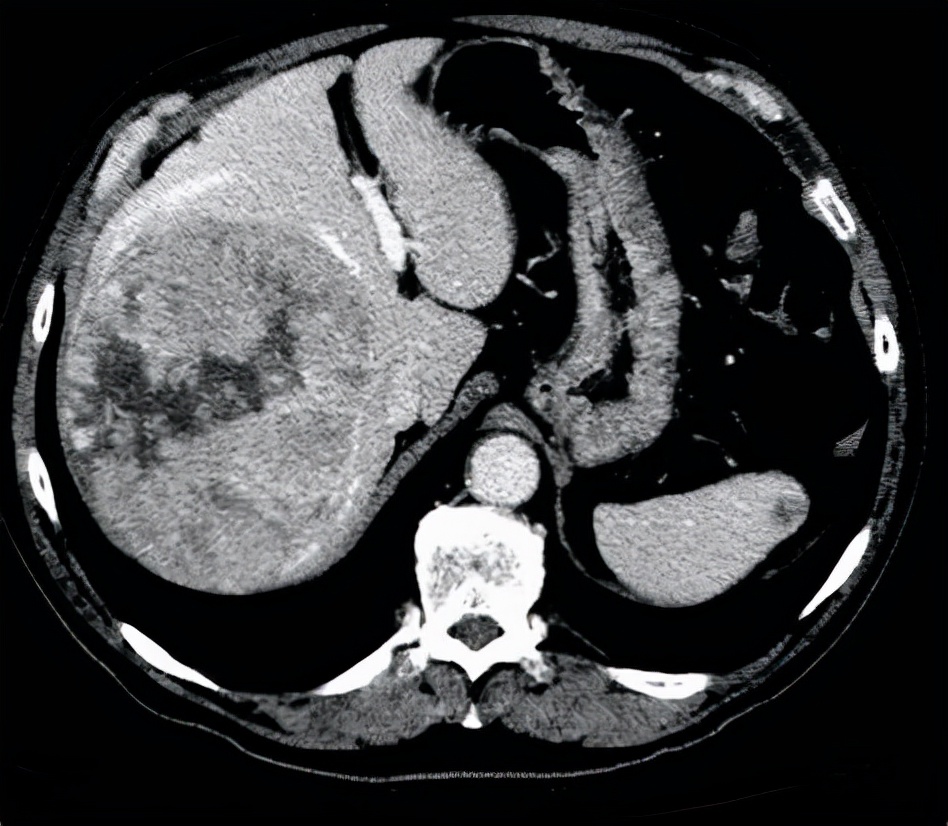

三、肚子越来越大:肝脏问题 。有的患者平时感觉挺健康的 , 不过在一段时间内 , 总感觉肚子越来越大了 , 肚子里面的水可能变多 。

这其实是一种非常不容易发现的水肿:腹水 。

如果出现了腹水 , 很多时候都是由肝脏疾病所导致的 , 所以腹水常常也都是很难治疗的 。

一般来说肝脏淋巴循环受阻或者门脉高压以及低白蛋白血症他们共同作用都会导致腹水的生成 , 所以治疗起来非常困难 。